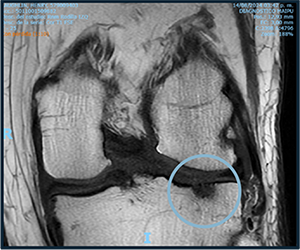

Before starting cell therapy, patients undergo a magnetic resonance imaging (MRI) or computed tomography (CT) scan to assess the condition of the bone and soft tissues of the knee.

PRE TREATMENT

August 13, 2023